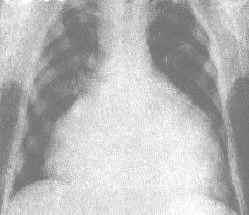

滲出性心包炎常為多發性漿膜炎的一部分,所見30例中合併胸膜炎或同時合併胸膜炎及腹膜炎者70%,因此,其他漿膜腔炎的存在有助於心包炎的診斷。X線檢查包括胸透可見心影擴大呈梨形,正常的心臟弧形消失,仰臥時心底部陰影增寬。心臟搏動減弱或消失。記波攝影對診斷有助。心電圖檢查可見QRS綜合波呈低電壓,竇性心動過速,T波平坦或倒置。超聲心動圖檢查,在左心室後壁與心包肺界面之間及左心室前壁與胸壁之間,出現液性暗區。積液量多時,右室前壁前方亦出現液性暗區,有心臟搖擺現象室間隔反常運動。結素試驗及身體他處結核病的存在有助於診斷。確診靠心包穿刺及心包積液中找到結核桿菌。在鑑別診斷方面需與化膿性心包炎、急性非特異性心包炎、風濕性心包炎、心肌病及心力衰竭相區別。根據典型的心臟壓塞症狀及體徵全面考慮,縮窄性心包炎的診斷並不困難。X線檢查和心臟超聲對診斷有幫助。胸透和X線攝影可見心臟搏動減弱,心緣曲線較為強直,上腔靜脈擴張,肺紋理增深,心包可有鈣化陰影。心電圖檢查有QRS波群低電壓和T波低、平或倒置,有診斷意義。超聲心動圖檢查可見左室後壁在心包區域有相距1~3cm平行運動的強烈回波,室間隔活動異常。鑑別診斷方面須與肝硬變、心肌病、充血性心力衰竭、滲出性心包炎及多發性漿膜炎、營養不良性水腫相區別。較難鑑別者為心內膜彈力纖維增生症,二者都是心臟舒張受限制,其血液動力學改變甚為相似,作者曾見1例5歲男孩,既往有結核史,縱隔淋巴結鈣化,曾長期被誤診為縮窄性心包炎,死後病理解剖證實為心內膜彈力纖維增生症。